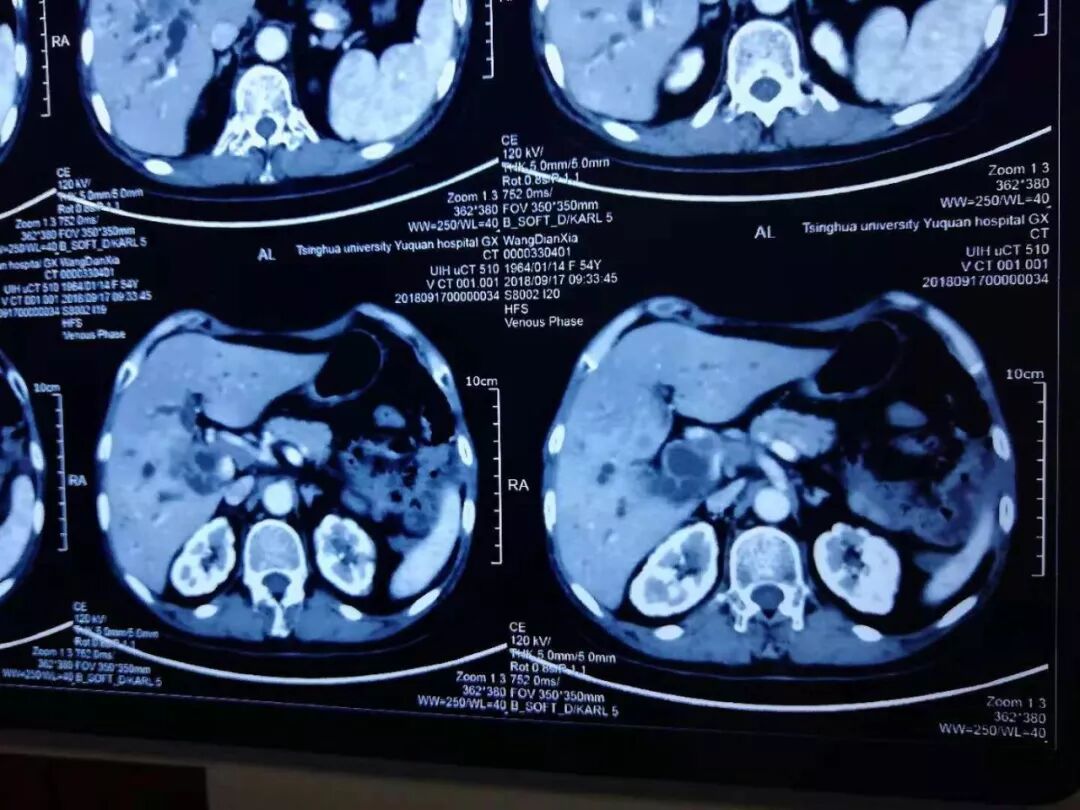

患者王某女性,54岁。患“急性胰腺炎”。后复继发肝内胆管扩张,肝门多发转移淋巴结,肝内多发乏血供小结节,转移瘤待除外。后期护理复杂,甚至可能死在手术台上,患者及家属内心十分恐惧,询问是否有其它解决办法,给予深部热疗,介入,臭氧治疗及靶向药物治疗以后,患者肿瘤明显缩小,一切恢复正常。

2018年9月17日检查CT:

臭氧治疗什么病三氧自体血疗法开启“慢性病、肿瘤”治疗新篇章_https://www.jmylbn.com_新闻资讯_第12张